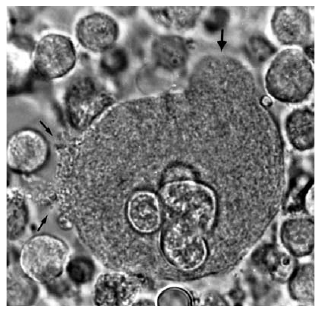

Figure2A